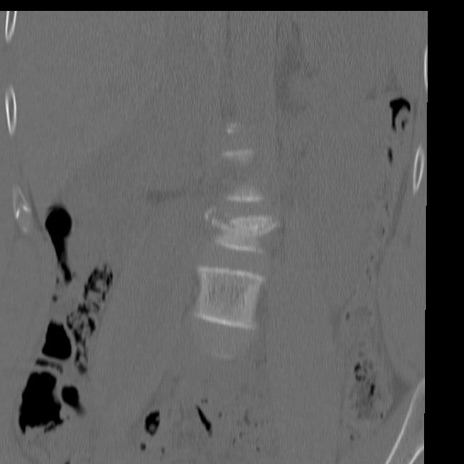

症例3 腰椎CT(冠状断像)

腰椎CT